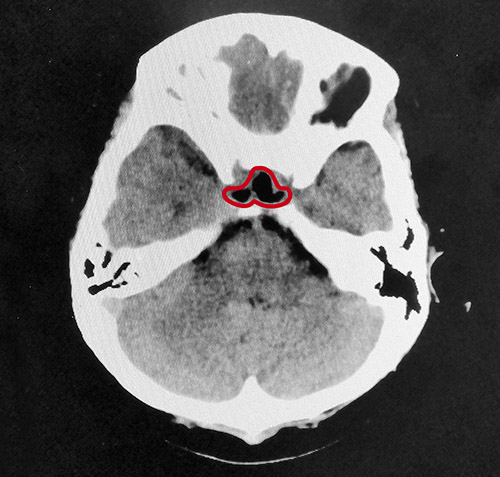

整個(gè)切除手術(shù)用時(shí)不到1小時(shí),術(shù)中出血量很少,腫瘤切除干凈。術(shù)后患者被醫(yī)護(hù)人員喚醒,被安全送到重癥監(jiān)護(hù)室監(jiān)護(hù)。經(jīng)鼻蝶竇入路垂體瘤切除微創(chuàng)手術(shù)具有腫瘤暴露佳,創(chuàng)傷和危險(xiǎn)性小,手術(shù)時(shí)間短、顱面外觀無損傷,手術(shù)效果好等優(yōu)點(diǎn),但該手術(shù)方式對專家的技術(shù)水平也有著非常高的要求。

▲術(shù)后影像:腫瘤切除干凈,鞍內(nèi)腦脊液填充